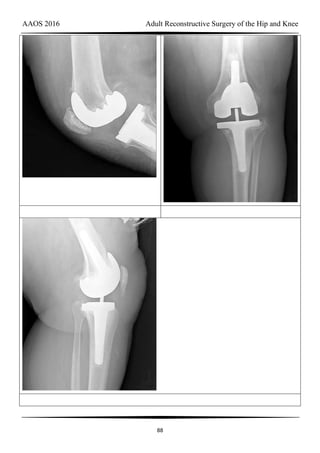

DISCUSSION

AAOS 2016 Adult Reconstructive Surgery of the Hip and Knee

18

Video 22 for reference

This patient has an unstable cruciate-retaining TKA. The tibial cut appears to be

substantial, necessitating a very thick polyethylene liner. In addition, the femoral component

may be slightly more proximally located. Tests for flexion-extension gap balancing would

indicate flexion instability. However, the possibility of infection remains, so screening blood

tests are appropriate. The surgical treatment for this unstable knee is revision TKA to a more

constrained implant, ensuring flexion-extension gap balancing. No evidence indicates that the

knee is infected. A thicker polyethylene insert will not adequately balance the knee.